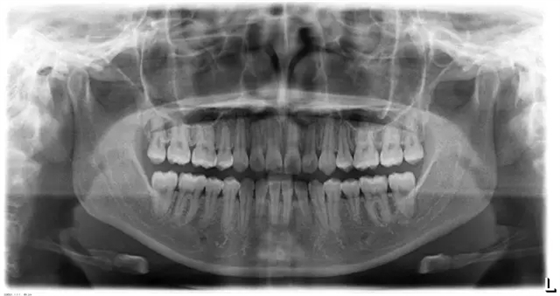

上下牙列擁擠,磨牙尖牙Ⅱ 類關(guān)系,3 度的深覆牙合,上頜中切牙伸長內(nèi)傾拔除上頜雙側(cè)的第一前磨牙,先粘上頜高轉(zhuǎn)矩的自鎖托槽排齊牙列,唇向開展上頜切牙,有一定的覆蓋,粘下頜標準轉(zhuǎn)矩托槽,上頜 1, 2 之間植入種植支抗壓入,同時后牙 5, 6 之間植入種植支抗內(nèi)收前牙,打開咬合關(guān)閉間隙。治療關(guān)鍵:前牙轉(zhuǎn)矩的控制第 1 個月 上頜粘上 Damon Q 高轉(zhuǎn)矩托槽,上 .014 熱激活 NiTi 絲。第 3 個月 上換 .014 x .025 熱激活 NiTi 絲。第 5 個月 上頜基本排齊,覆蓋增大,上換 .017 x .025 NiTi絲,下頜粘托槽,下 .014 熱激活 NiTi 絲。第 7 個月 上 .017 x .025 NiTi 絲加搖椅,下?lián)Q .014 x .025 熱激活 NiTi 絲第 9 個月 上頜換 .019 x .025 NiTi 絲加搖椅,下頜換 .017 x .025 NiTi 絲第 11 個月 下頜換 .019 x .025 加搖椅,上頜 1, 2 之間, 5, 6 之間植入種植釘,下頜出現(xiàn)散隙。第 13 個月 上頜換 .019 x .025ss 加搖椅,前牙種植釘用 Power Chain 壓低前牙(每側(cè) 100g),后牙種植釘關(guān)閉間隙(每側(cè) 150g),下?lián)Q .019 x .025ss,Power Chain 關(guān)閉間隙。第 19 個月 上頜前牙基本壓低到位去除前牙種植釘,繼續(xù)用關(guān)閉間隙,下頜散隙關(guān)閉。

第 22 個月 上頜覆蓋變小,去除 5, 6 之間種植釘,后牙前移關(guān)閉間隙。第 30 個月 患者未配合中線牽引,下中線仍有 1mm 右偏,患者對矯治效果滿意要求拆除,拆除固定矯治器,取模制作壓模保持器。 1.骨性 Ⅱ 類的患者內(nèi)收前牙時需對上頜前牙的轉(zhuǎn)矩進行較好的控制才能獲得良好的面型和唇部形態(tài)。 2.露齦笑的患者治療前要分析其病因是唇、牙齦、牙齒、牙槽骨、上頜骨或多種因素結(jié)合,再制定矯治方案。 3.Ⅱ 類第二分類伴露齦笑的患者的上頜前牙移動軌跡是唇向開展-壓低-整體內(nèi)收。 4.Ⅱ 類第二分類牙齒舌傾比較厲害的情況,上頜中切牙慎用樹脂咬合墊。 5.壓低前牙或控根移動時容易發(fā)生牙根的吸收,需輕力緩慢的移動。